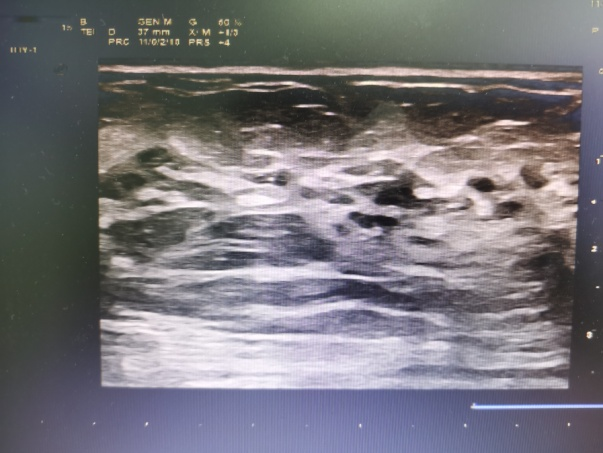

乳腺b超图

超声医生告诉你:发现乳腺结节,该怎么办?